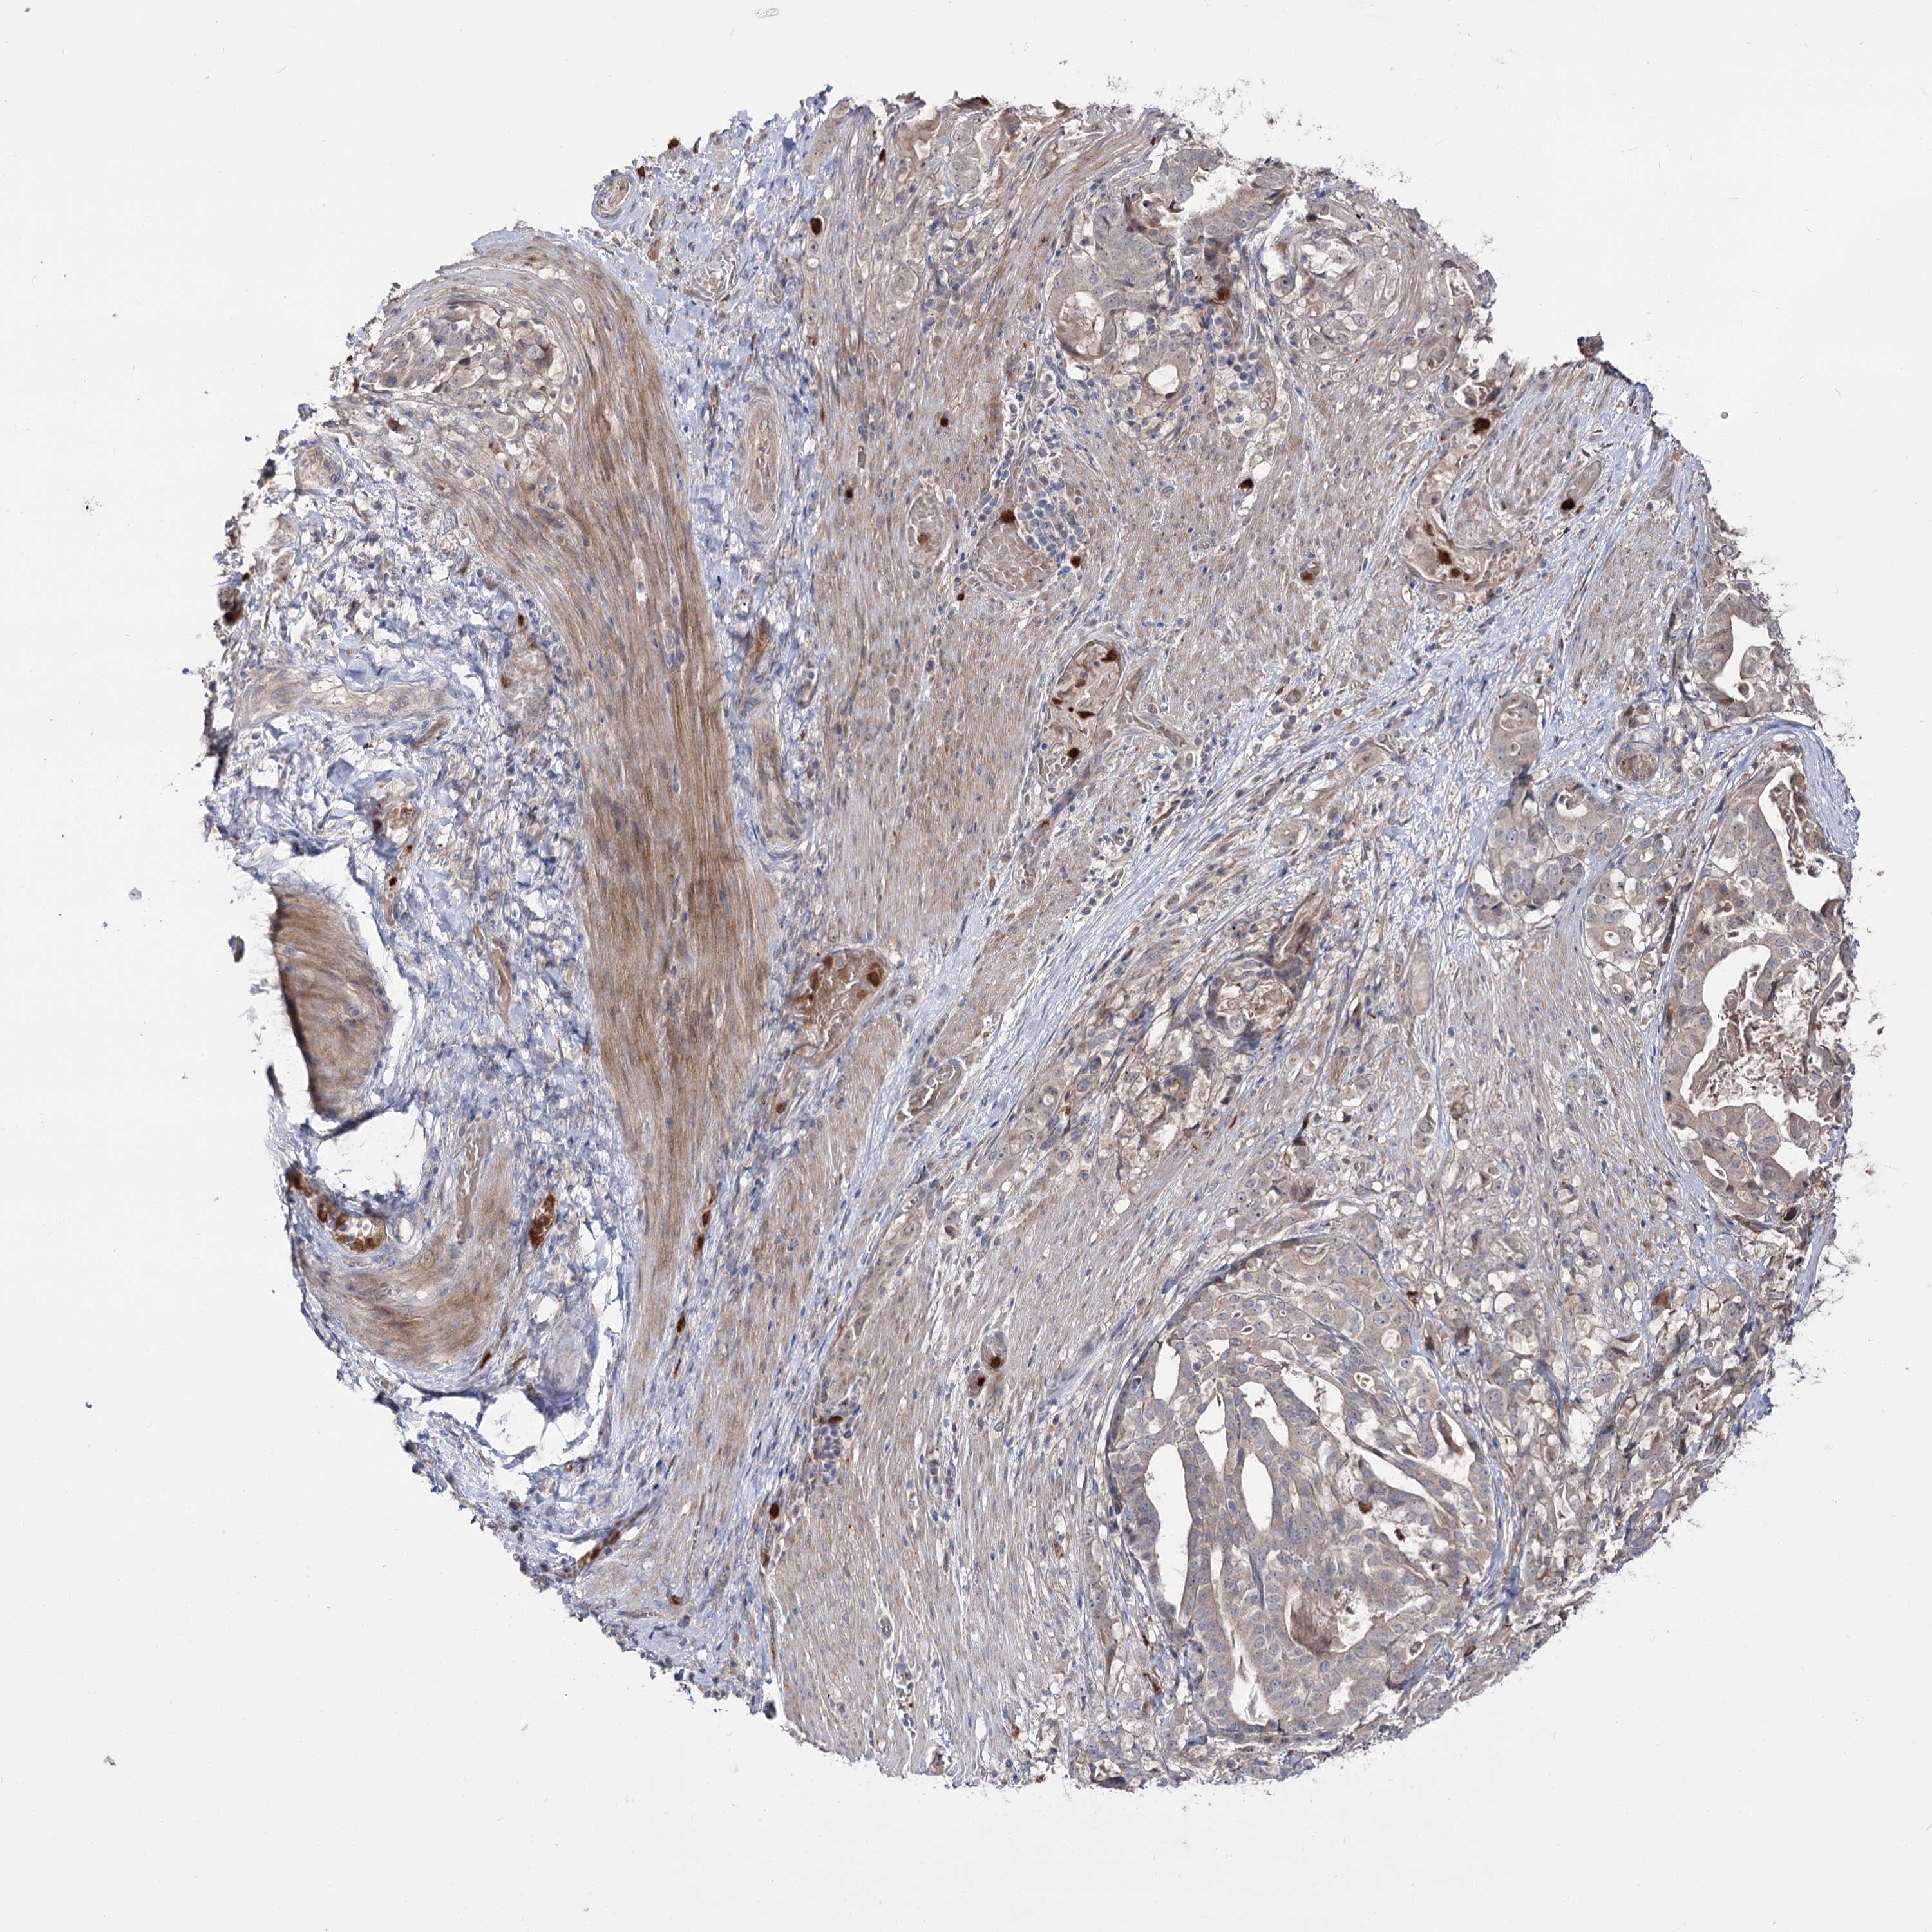

STOMACH CANCER - Protein expressioni

A mouse-over function shows sample information and annotation data. Click on an image to view it in a full screen mode. Samples can be filtered based on level of antibody staining by selecting one or several of the following categories: high, medium, low and not detected. The assay and annotation is described here.

Note that samples used for immunohistochemistry by the Human Protein Atlas do not correspond to samples in the TCGA dataset.

Antibody stainingi

Antibody staining in the annotated cell types in the current human tissue is reported as not detected, low, medium, or high, based on conventional immunohistochemistry profiling in selected tissues. This score is based on the combination of the staining intensity and fraction of stained cells.

Each image is clickable and will lead to virtual microscopy that enables deeper exploration of all samples and also displays staining intensity scores, fraction scores and subcellular localization as well as patient and tissue information for each sample.

Antibody HPA038040

Staining

High

Medium

Low

Not detected

Intensity

Strong

Moderate

Weak

Negative

Quantity

>75%

75%-25%

<25%

None

Location

Nuclear

Cytoplasmic/membranous

Cytoplasmic/membranous,nuclear

Adenocarcinoma, NOS

Adenocarcinoma, High grade